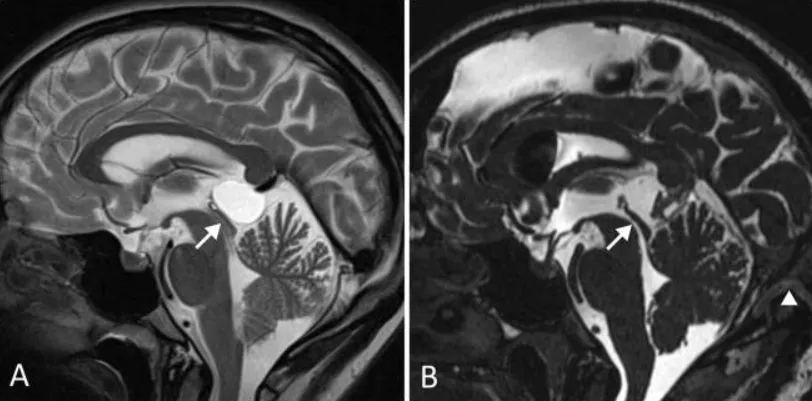

术前(A)及术后(B)正中矢状位MR CISS成像显示:松果体囊肿导致中脑导水管狭窄(箭头所示),但未引发脑积水。术后正中矢状位MR CISS图像(B)显示:囊肿完全切除,中脑导水管通畅。开颅手术范围达横窦(箭头标示)。患者症状完全消失。